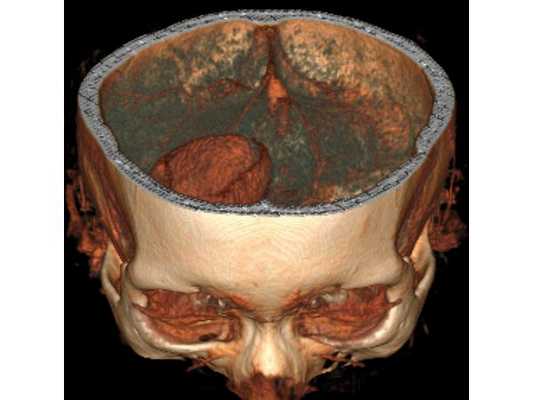

3D-реконструкция объёмного образования правой лобной доли головного мозга, выполненная на основании сканов КТ с контрастным усилением

На основании диагноза проведена краниотомия (трепанация черепа) и удаление абсцесса правой лобной доли: ⠀• выполнен дугообразный разрез мягких тканей в правой лобно-височной области; ⠀• наложено фрезевое отверстие у основания скулового отростка лобной кости, из которого краниотомом выпилен костный лоскут 6*5 см; ⠀• для остановки кровотечения использован хирургический воск и электрокоагуляция по ходу доступа; ⠀• произведено подковообразное вскрытие твёрдой мозговой оболочки основанием к сагиттальному синусу: абсцесс был хорошо отграничен капсулой и подпаянной к коре головного мозга твёрдой мозговой оболочкой; ⠀• тонким шпателем твёрдая мозговая оболочка постепенно отделена от коры, абсцесс вскрыт — получен гной, внешне напоминающий сливки, с гнилостным запахом; ⠀• аспирировано (удалено) около 60 мл гноя; ⠀• полость абсцесса многократно промыта водными растворами перекиси водорода и фурацилина, мозг запал, имеется хорошая пульсация; ⠀• твёрдая мозговая оболочка ушита, по периметру подшито трепанационное окно, костный лоскут уложен на место, на рану наложены послойные швы и асептическая повязка. При оперативных вмешательствах по поводу абсцесса головного мозга принято оставлять дренаж в полости абсцесса. Однако, с учётом наличия хорошо сформированной капсулы, которая была визуализирована после промывания полости антисептическими растворами, принято решение не оставлять дренаж.